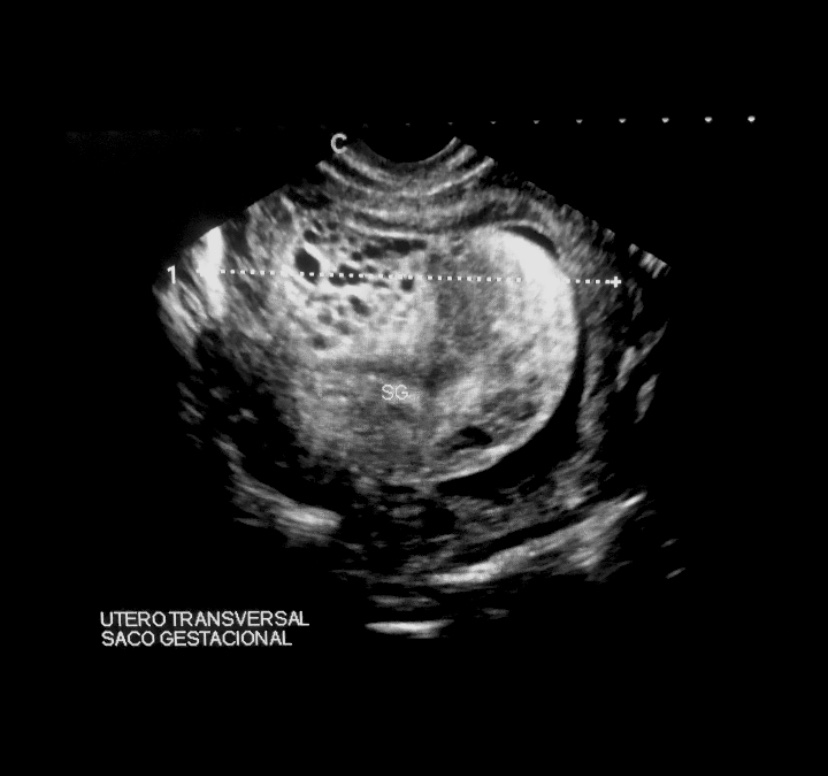

Incomplete moles have Triploid genotype (69XXY, 69XXX) usually contains fetal/embryonic tissue/cells. hCg usually <100,000

<5% become invasive

Case 3